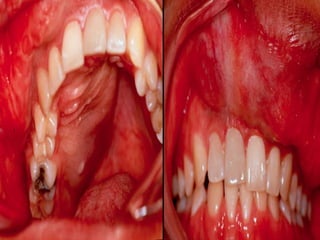

Peripheral Odontogenic Fibroma to arise from odontogenic epithelial rests in the periodontal ligament or the attached gingiva itself.  The entity, formerly confused with peripheral cemento-ossifying fibroma, is considered to be the extraosseous counterpart of the central odontogenic fibroma of the World Health Organization type.  A peripheral odontogenic fibroma manifests as a firm, slowly growing, sessile, and nodular growth of the gingiva, most often on the mandibular buccal or labial aspect as depicted below.  wide age range and affects both sexes equally.

Peripheral Odontogenic Fibroma DDX of a peripheral odontogenic fibroma  inflammatory gingival hyperplasia  peripheral cemento-ossifying fibroma  peripheral giant cell granuloma  Microscopically: unencapsulated mass of interwoven cellular fibrous connective tissue that contains scattered nests or strands of odontogenic epithelium. Myxoid foci, osteoid, cementoid, or dystrophic calcifications are sometimes seen.  Treatment : conservative excision & reestablish the gingival architecture and periodontal integrity.

• #107 The clinical differential diagnosis of a peripheral odontogenic fibroma includes inflammatory gingival hyperplasia, peripheral cemento-ossifying fibroma, and peripheral giant cell granuloma Microscopically, the tumor consists of an unencapsulated mass of interwoven cellular fibrous connective tissue that contains scattered nests or strands of odontogenic epithelium. Myxoid foci, osteoid, cementoid, or dystrophic calcifications are sometimes seen. The surface generally is not ulcerated. Treatment consists of conservative excision performed with care to maintain or reestablish the gingival architecture and periodontal integrity. Recurrence is rare